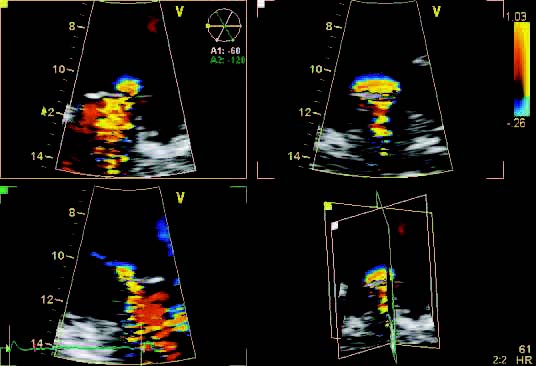

- Color Doppler

- Power Doppler

- Duplex

- Triplex

- Dual screen

- Quad screen